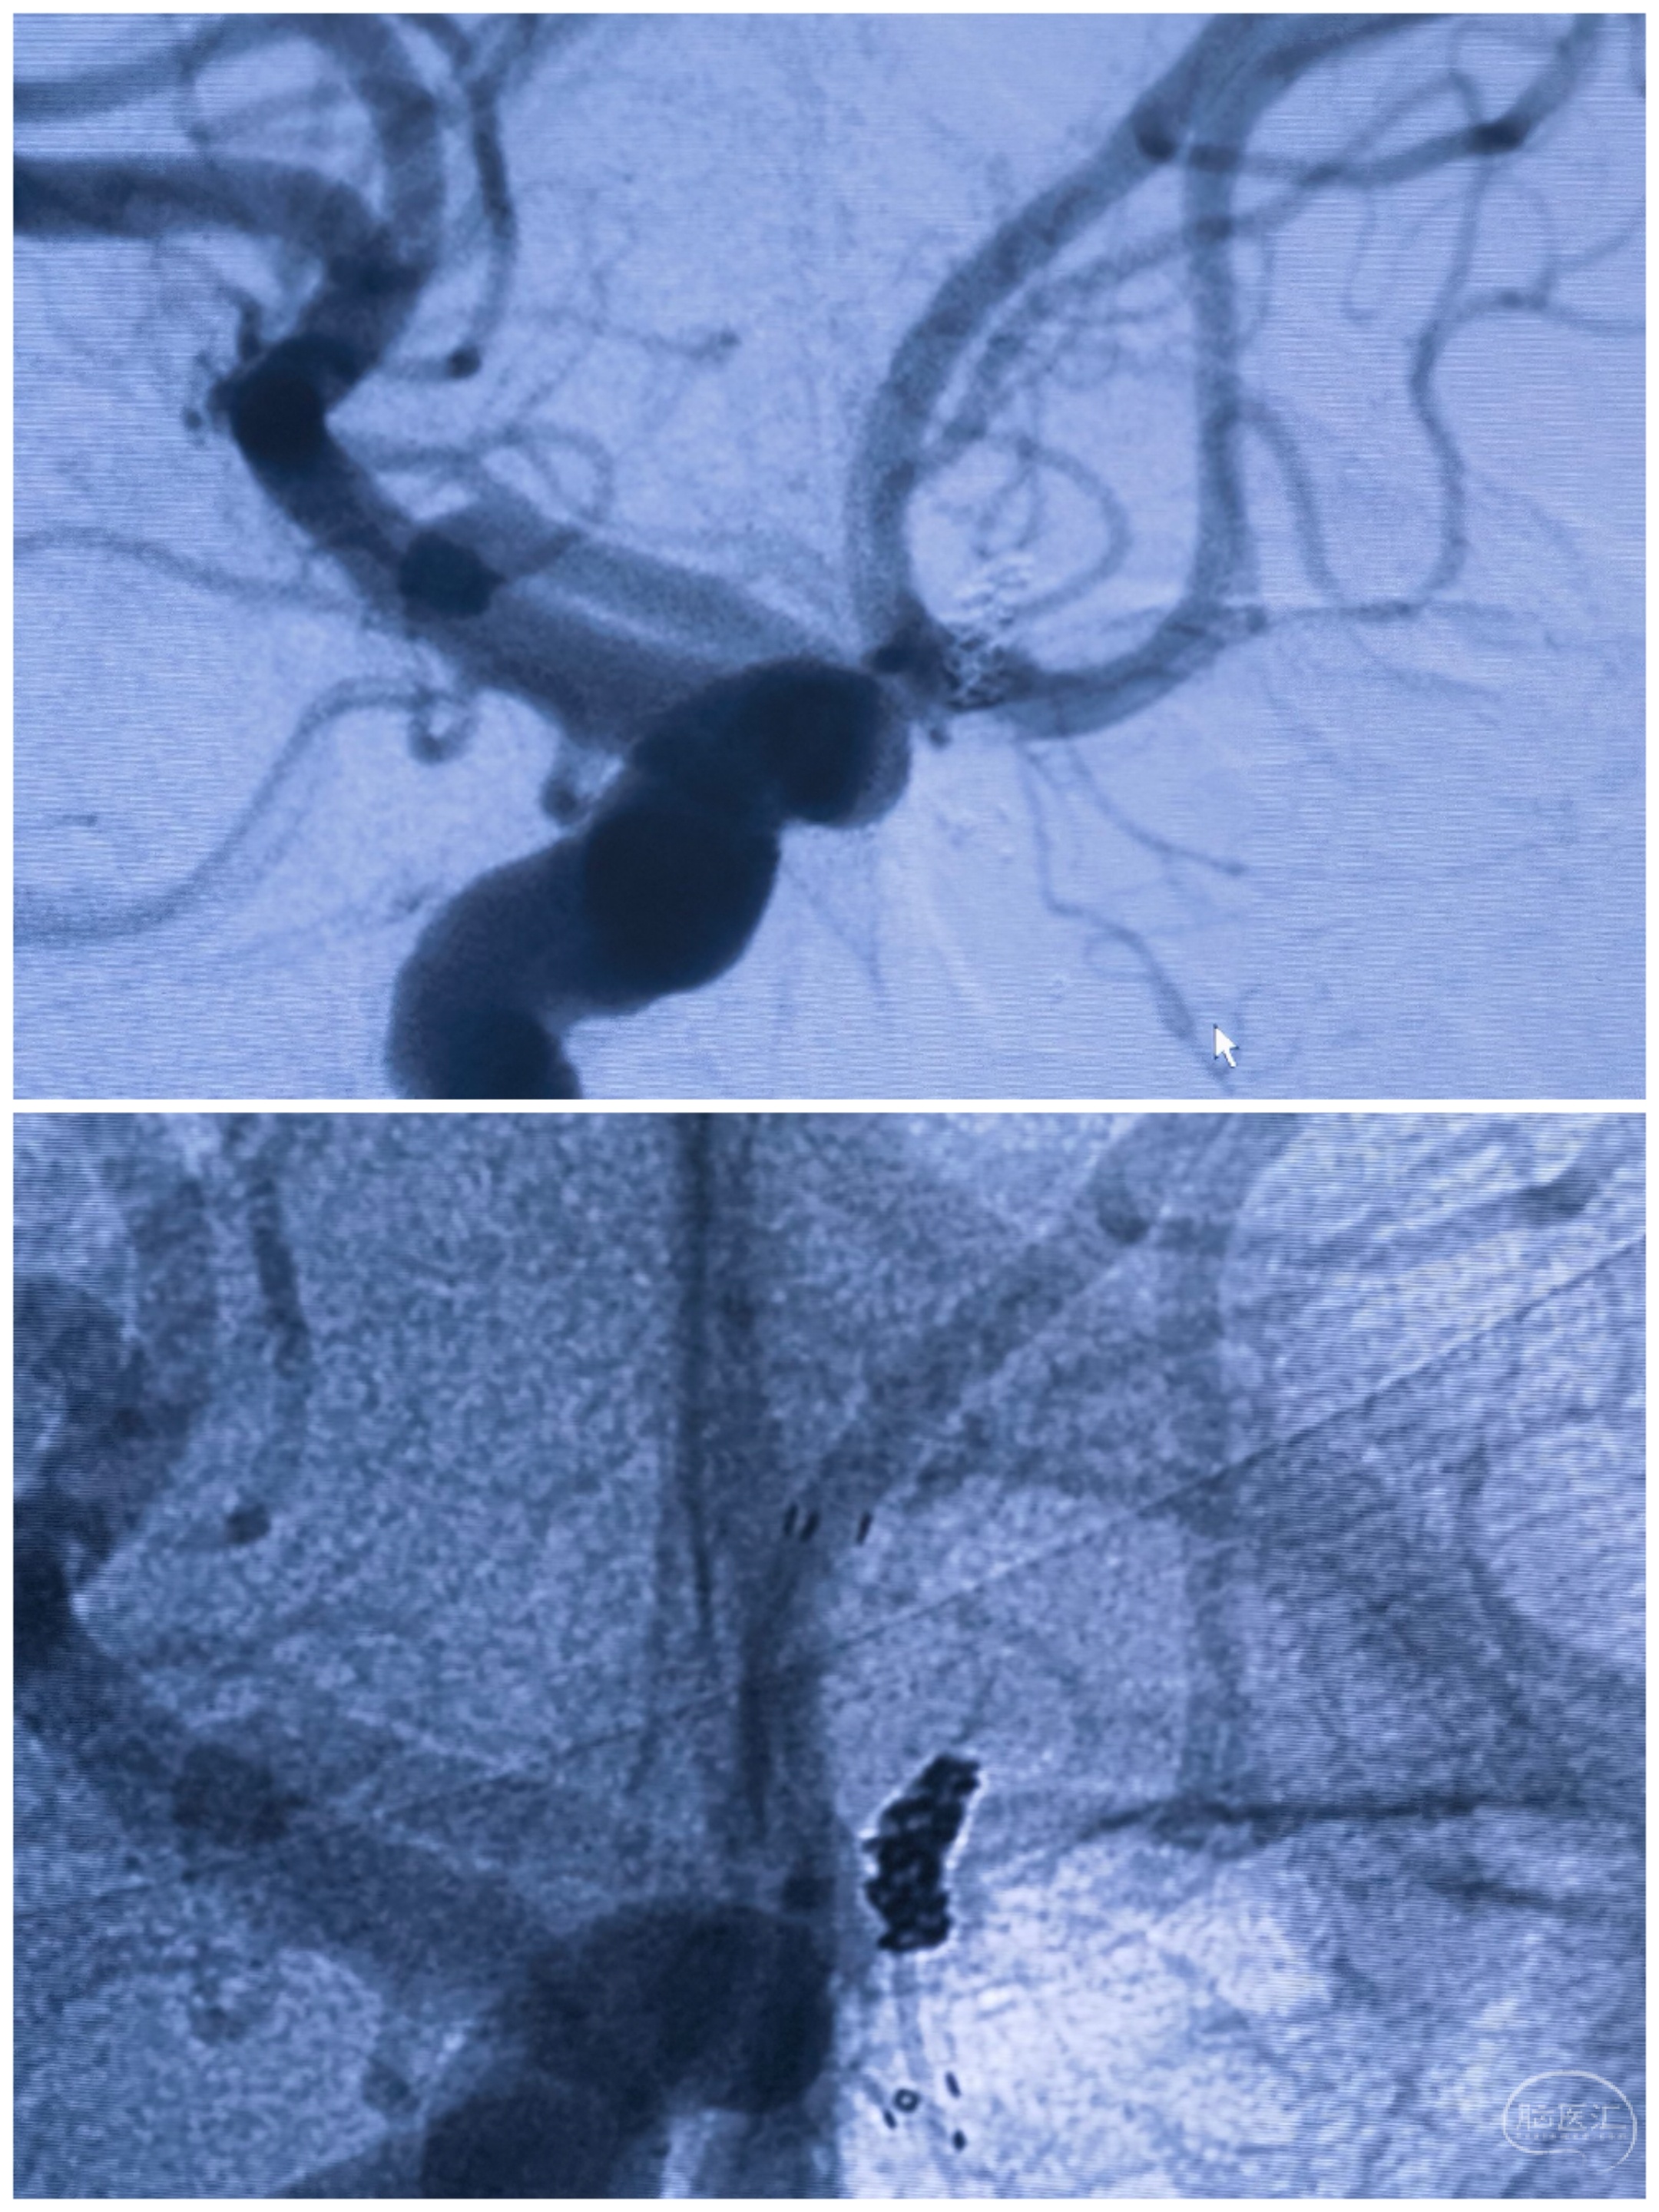

术后栓塞情况

术后左侧3D旋转造影

术后右侧3D旋转造影

术后3D重建情况:动脉瘤未显影,双侧大脑前-前交通动脉保留完好